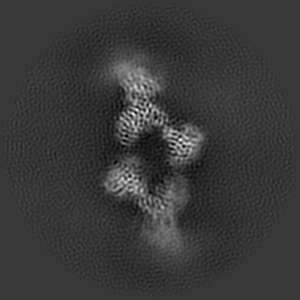

CryoEM structure of non-neutralizing bivalent antibody CBH-4B in complex with Hepatitis C virus envelope glycoprotein E2

Cryo-EM structures of HCV E2 glycoprotein bound to neutralizing and non-neutralizing antibodies determined using bivalent Fabs as fiducial markers.